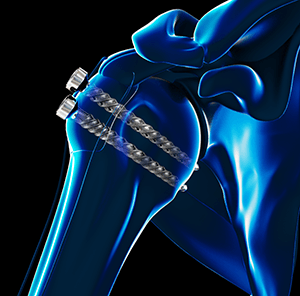

• Revision Rotator Cuff Repair

Img-Revision Rotator Cuff Repair

Rotator cuff repair is a surgery to repair an injured or torn rotator cuff.